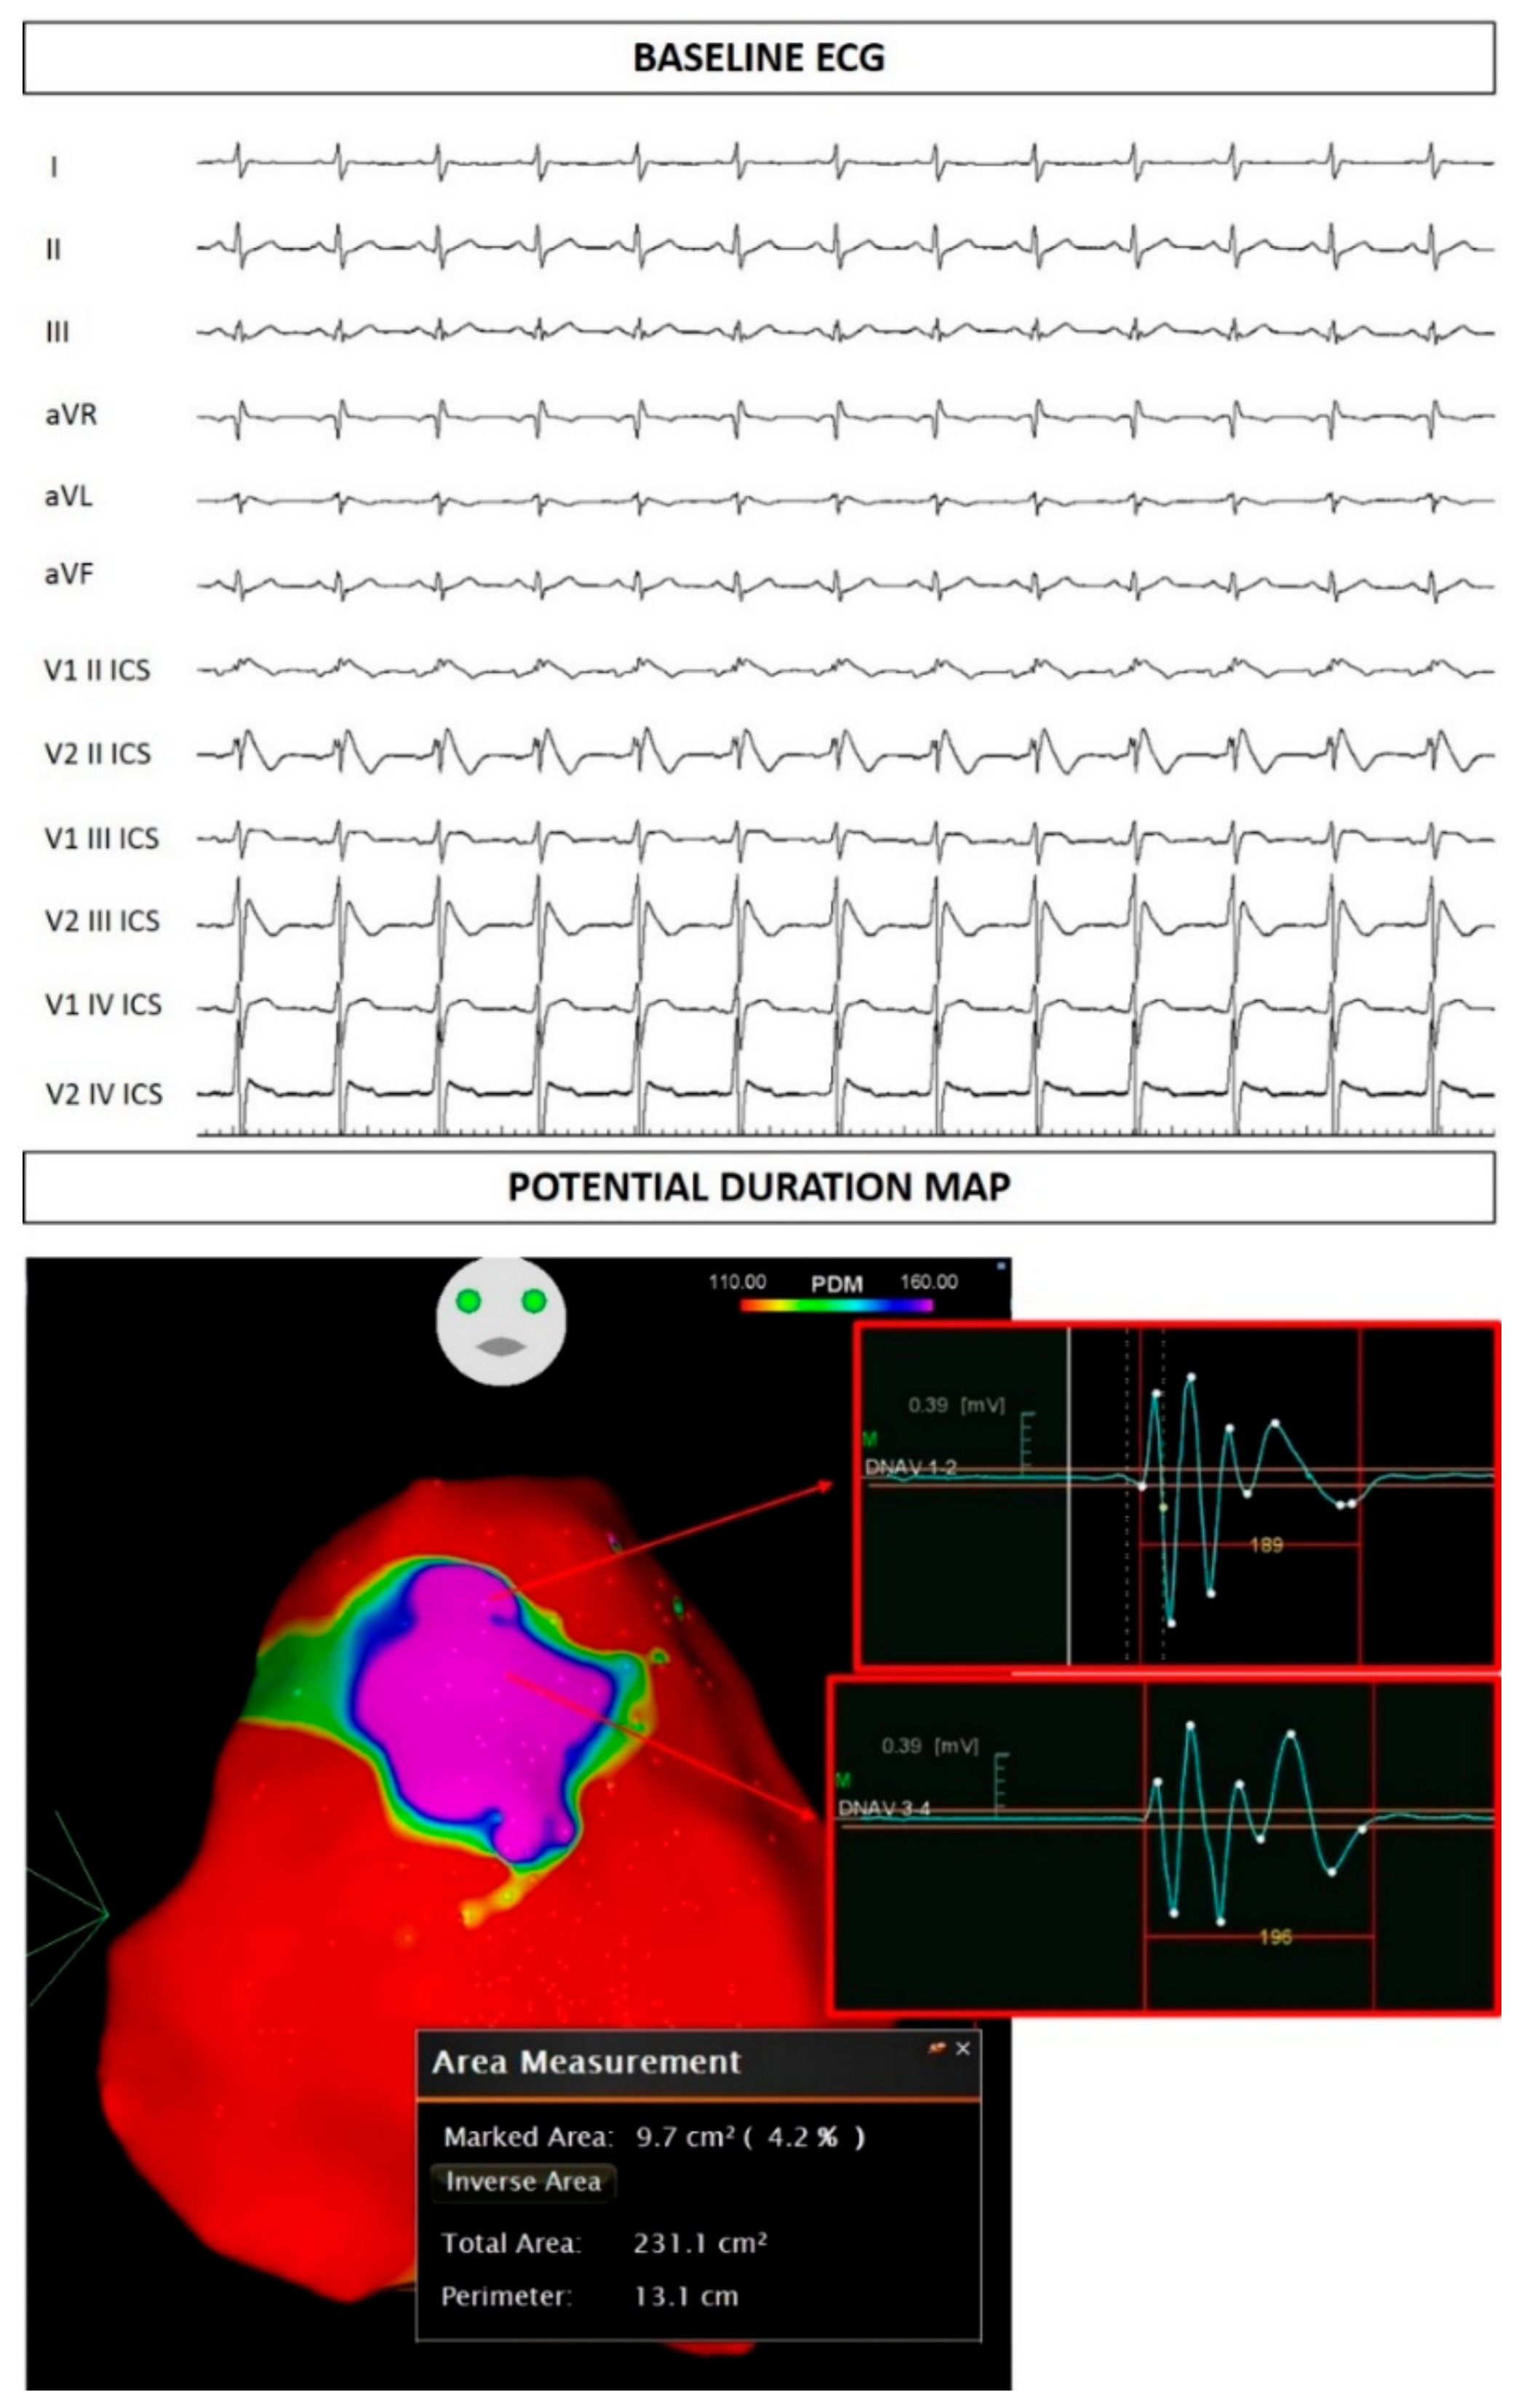

2.1. Case Presentation

2.2. Assessment of Family Members